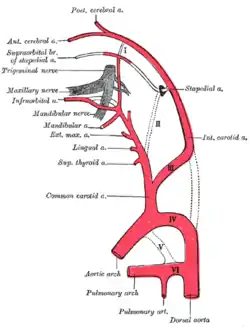

Diagram showing the origins of the main branches of the carotid arteries.

Diagram showing the origins of the main branches of the carotid arteries. The internal carotid and vertebral arteries. Right side. (Superior thyroid visible at center.)